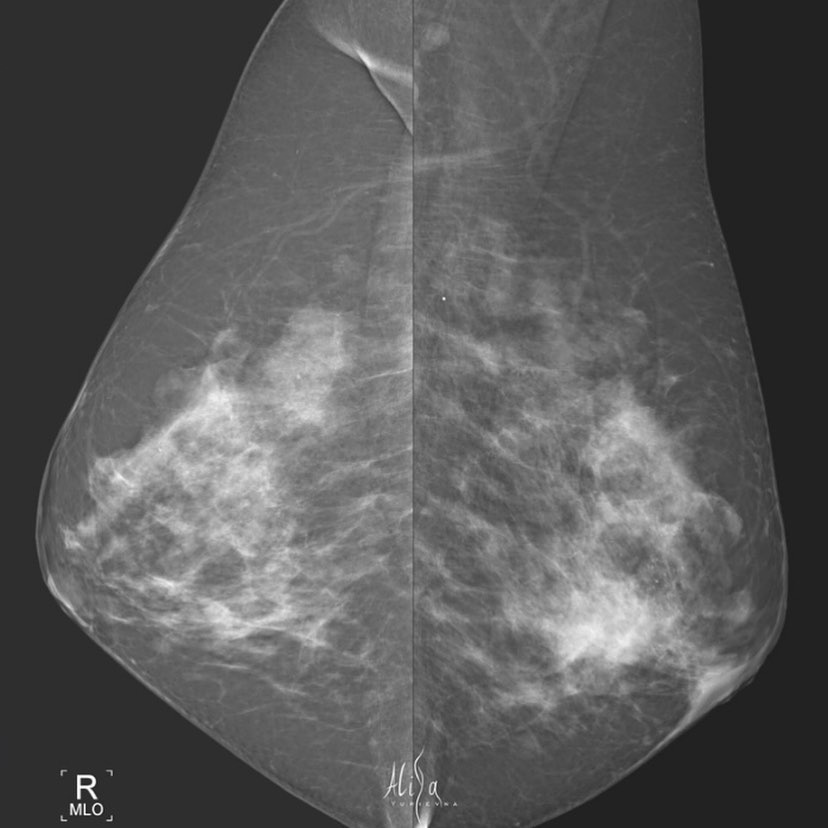

Женщина 1965гр Клинически - ЗН слева во внутреннем квадранте Маммография - синхронный рак Гистология: Инвазивная карцинома молочной железы G3. ⠀ Всё нашли?) наглядно и не сложно💚 #маммография #маммографияекб #диагностика #ракмолочнойжелезы #рентгенология #берегисебя #екатеринбург #синхронныйрак

Женщина 1965гр

Клинически - ЗН слева во внутреннем квадранте

Маммография - синхронный рак

Гистология:

Инвазивная карцинома молочной железы G3.